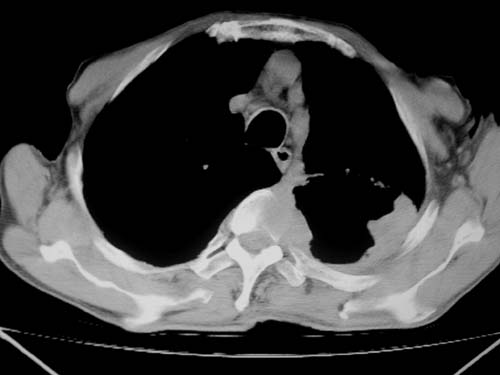

标题: CT19736:男,76岁,咳嗽,胸痛 [打印本页]

标题: CT19736:男,76岁,咳嗽,胸痛

支持左上肺周围型肺癌性并空洞形成伴胸椎转移。

左上沟癌空洞形成并胸椎转移。

支持 左上肺周围型肺癌性并癌性空洞形成伴胸椎转移。

左上肺癌性空洞伴胸椎转移。